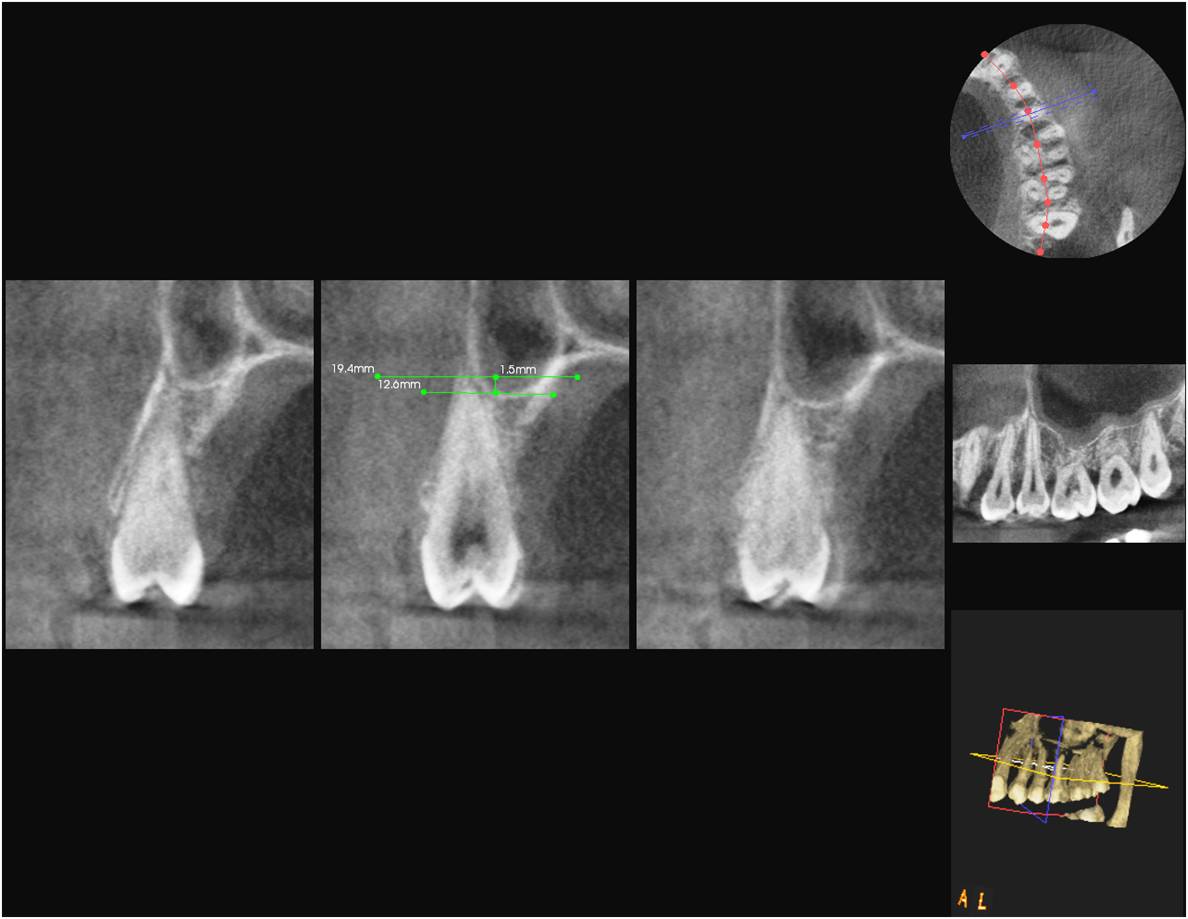

Results: In cases of classification 0, 85% and in classification 1 , 55.3% cases shows similar classification in both OPG and DVT. 28.5% of cases in both imaging modalities show classification 2. Only 15.9% of teeth roots exhibits classification 3. 11.1% of cases showed classification 4.The panoramic radiograph showed a statistically significant 2.24 times longer root projection on the sinus cavity in OPG comparison to DVT images.

Conclusion: Teeth roots projecting in to the sinus in OPG, shows no vertical protrusion in to the sinus in DVT images. Hence DVT was better than OPG with measurements that were more exact and closer to anatomical reality.